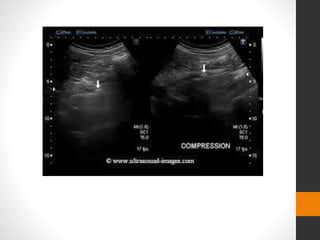

Ultrasound

Extensively used in trauma.

โ€ข Subcapsular and perinephric haematoma can be seen

โ€ข Acutely seen as echo-poor areas, becoming more

heterogeneous and echogenic with time.

โ€ข Disruption of renal parenchyma with capsular tears.

โ€ข Color flow and spectral Doppler may allow diagnosis of

pedicle injuries.

โ€ข Significant renal injuries may be missed, with up to 80%

of parenchymal lesions being overlooked.